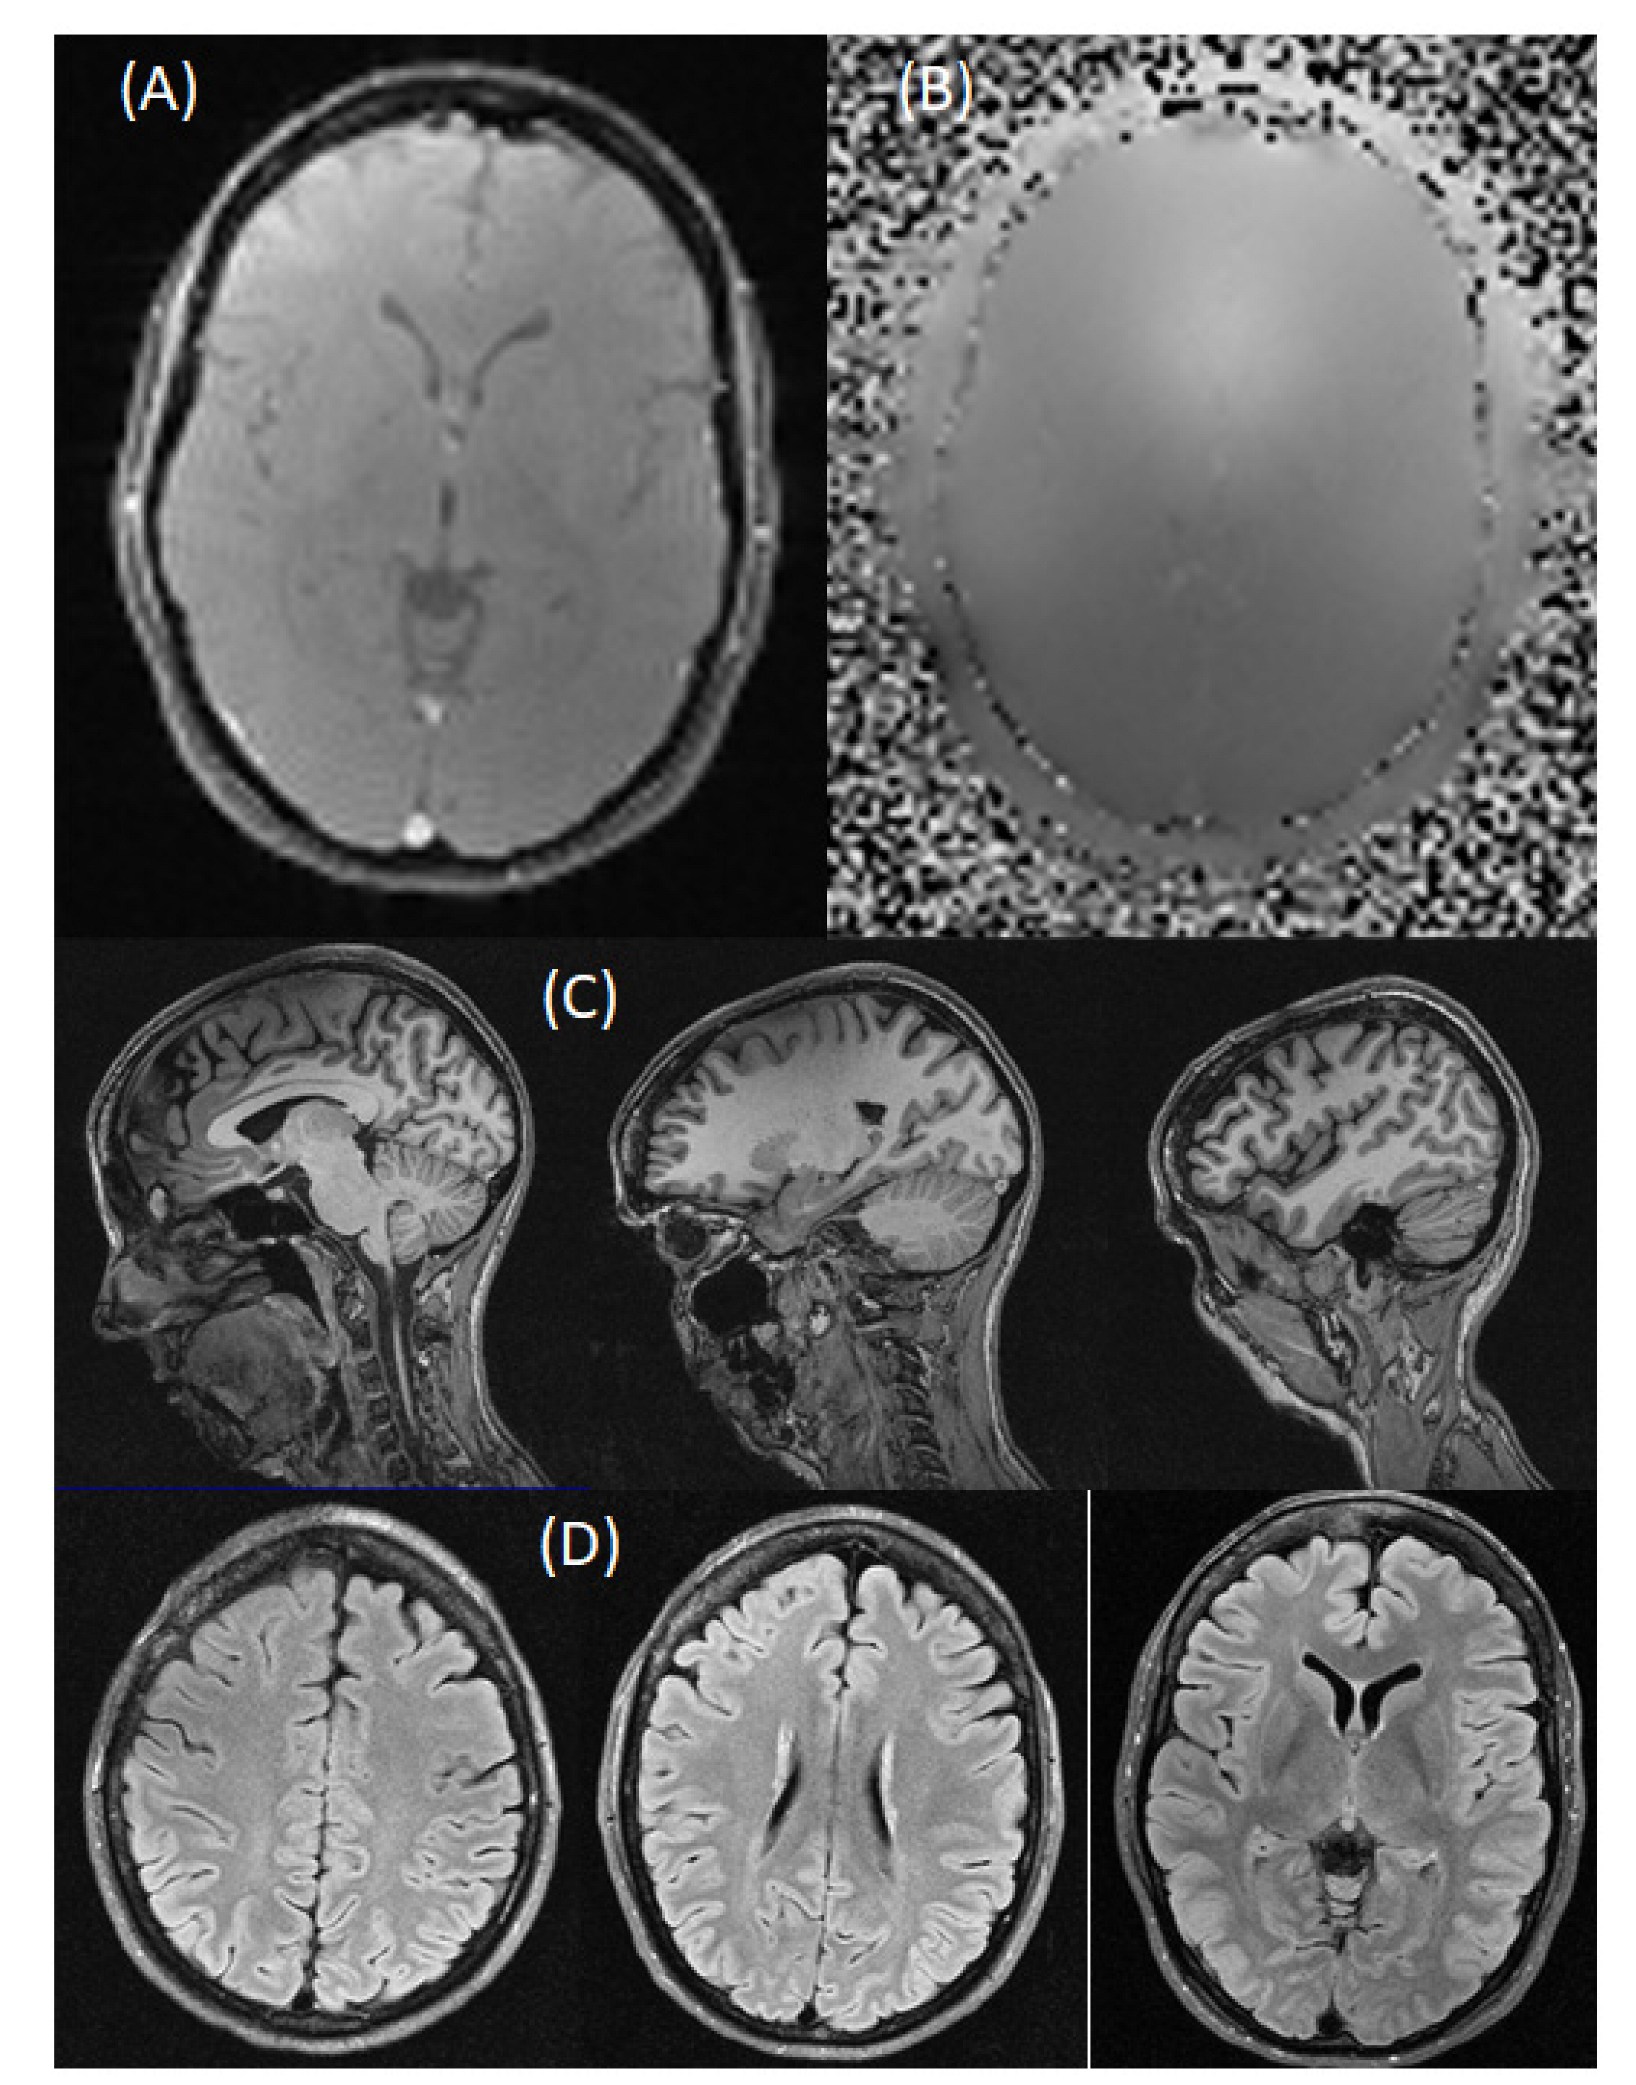

2.3. MRI Imaging

2.3.1. Phantom Imaging

2.3.2. Human Imaging

3. Results